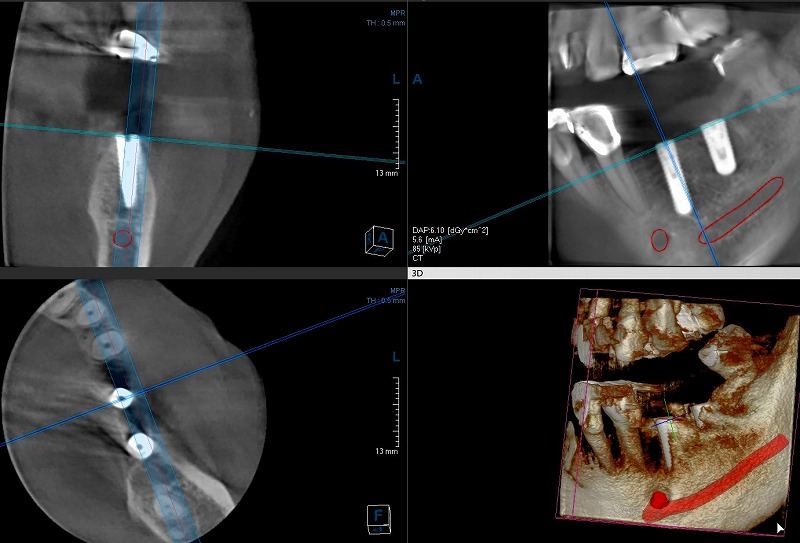

下のレントゲン写真はCTの写真です。左下が水平の断面で上の二つが前からと横からの垂直断面です。

この方の場合は中間の奥歯が2本無くなっています。インプラントの両サイドに歯が残っているとドリルのガイドも安定しやすく、予定した位置に綺麗に入れる事が可能です。赤いラインは下顎の真中に通っている太い神経の管で下顎管と言いますが、インプラントが神経を避けて綺麗に入っています。

この神経を傷つけるとしびれが残ったりします。問題が発生する時の多くは、ガイドを信用し過ぎて掘りすぎてしまうことです。